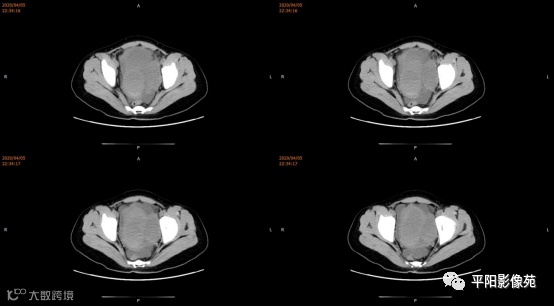

3.CT检查 对子宫、阴道的界限区分有一定限制,对子宫内膜、肌层难以分辨,故CT对子宫先天性异常的研究较少。阴道闭锁时,若宫腔内经血潴留,可见液性低密度聚集,子宫肌层密度均匀。